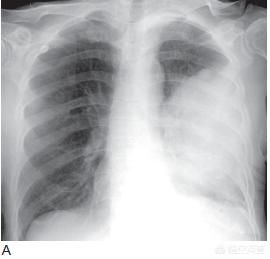

En général, l'enrouement peut être guéri spontanément au bout d'un certain temps ou après une période de traitement. Si l'enrouement va et vient, qu'il est récurrent et qu'il reste difficile à guérir après un traitement anti-inflammatoire, on considère généralement qu'il est dû à l'effet inhibiteur du cancer du poumon avancé sur le nerf laryngé récurrent, et il est alors suggéré que le patient subisse un scanner ou d'autres examens radiologiques afin de déterminer la taille de la tumeur ainsi que la profondeur de l'infiltration, et de clarifier s'il y a prolifération ou métastase.

Si l'enrouement d'un patient atteint d'un cancer du poumon s'aggrave progressivement sans aucun signe d'amélioration, il est pratiquement certain qu'il est causé par la tumeur qui comprime ou empiète sur le nerf laryngé récurrent ; un scanner du thorax et une laryngoscopie peuvent alors être effectués pour clarifier l'état de la maladie. Si la laryngoscopie révèle une paralysie des cordes vocales, il est certain que le nerf laryngé récurrent est endommagé. Si le nerf laryngé récurrent est seulement comprimé, il peut être détaché chirurgicalement, mais il n'y a pratiquement aucune chance d'intervention chirurgicale en cas d'invasion du nerf laryngé récurrent causée par une tumeur maligne. L'invasion du nerf laryngé récurrent par un cancer central du poumon ou la compression du nerf laryngé récurrent par des ganglions lymphatiques médiastinaux signifie que la tumeur est avancée.